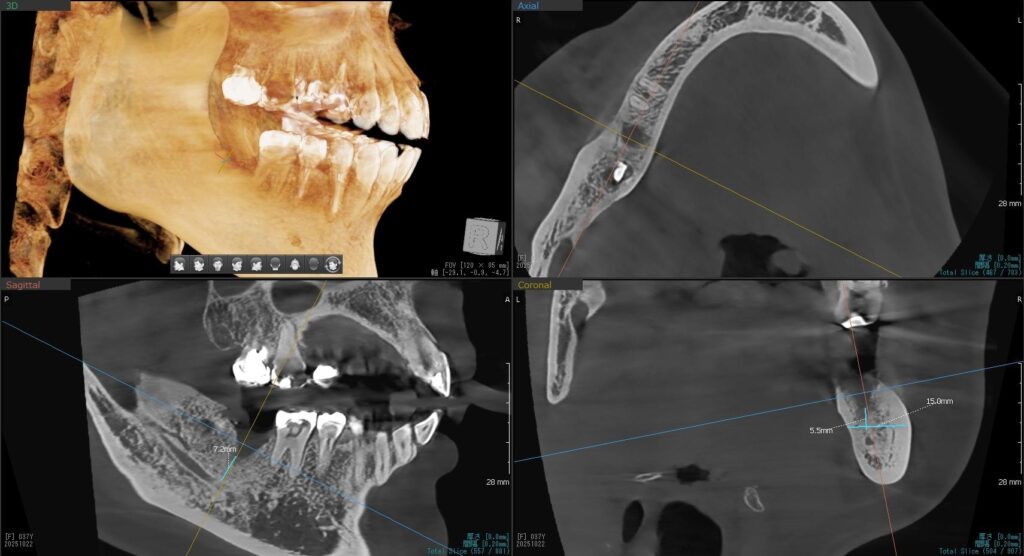

今回の患者様はインプラント植立を希望され、右下7番目の植立が決まりました。

ドリルの先端を細い物から徐々に大きい物に変えながら、植立するインプラント体のネジの部分を除いた胴の部分の太さに合わせた大きさの穴を開けていきます。

開けた穴に、専用道具を使ってネジを締めるように長さ2センチ程のインプラントを骨に埋め込んでいきます。

しっかりとインプラント埋め込まれた後は、動揺がないか、噛んだ時に当たらないかなどを確認して、最後にパノラマ写真を撮影して今回のオペは終了となりました。